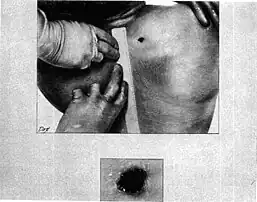

- The Bethesda autopsy physicians attempted to probe the bullet hole in the base of Kennedy's neck above the scapula, but failed as it had passed through neck strap muscle. They did not perform a full dissection or persist in tracking, as throughout the autopsy they were unaware of the exit wound at the front of the throat. Emergency room physicians had obscured it while performing the tracheotomy.

- At Bethesda, the autopsy report of the president, Warren Exhibit CE 387,[37] described the back wound as being oval-shaped, 6 by 4 millimeters (0.24 in × 0.16 in), and located "above the upper border of the scapula" (shoulder blade) at a location 14 centimeters (5.5 in) from the tip of the right acromion process, and 14 centimeters (5.5 in) below the right mastoid process (the bony prominence behind the ear).

- The concluding page of the Bethesda autopsy report[37] states that "[t]he other missile [the bullet to the back] entered the right superior posterior thorax above the scapula, and traversed the soft tissues of the supra-scapular and the supra-clavicular portions of the base of the right side of the neck."

- The report also said that there was contusion (i.e., a bruise) of the apex (top tip) of the right lung in the region where it rises above the clavicle, and noted that although the apex of the right lung and the parietal pleural membrane over it had been bruised, they were not penetrated. This indicated passage of a missile close to them, but above them. The report pointed out that the thoracic cavity was not penetrated.

- This bullet produced contusions both of the right apical parietal pleura and of the apical portion of the right upper lobe of the lung. The bullet contused the strap muscles of the right side of the neck, damaged the trachea, and exited through the anterior surface of the neck.